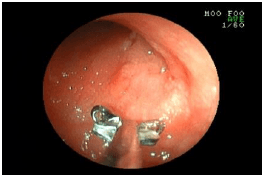

内視鏡を使った呼吸器の検査

内視鏡は胃腸以外にも、喉や気管などの呼吸器の検査・処置にも使われます。

![]() 気管の入り口 |